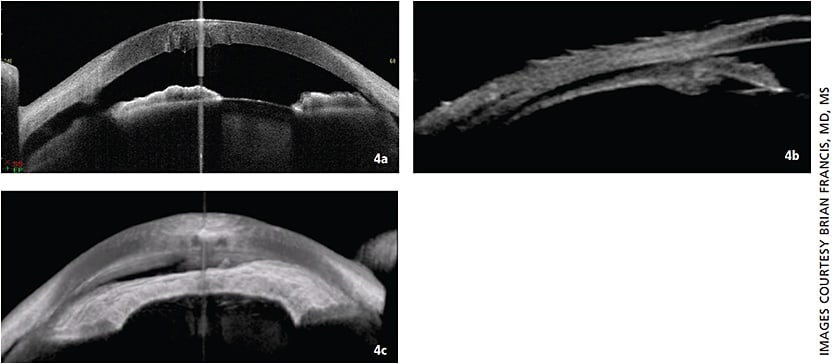

UBM and AS-OCT preoperatively helped make the diagnosis of a cyclodialysis cleft. The SS-AS-OCT allowed for complete viewing of the cyclodialysis cleft opening, which assisted in surgical planning.

CASE 2: Figure 4a. Anterior segment OCT demonstrates disinsertion of the iris root and fluid in the suprachoroidal space. An advantage of AS-OCT is its higher resolution. You can see the areas of Descemet folds and corneal edema anterior to each fold. Figure 4b. UBM shows fluid in the suprachoroidal space entering through the cleft. The UBM also shows that the ciliary body is detached in addition to the iris root. Figure 4c. Swept Source AS-OCT combines multiple AS-OCT images to create a three-dimensional view of the cyclodialysis cleft.